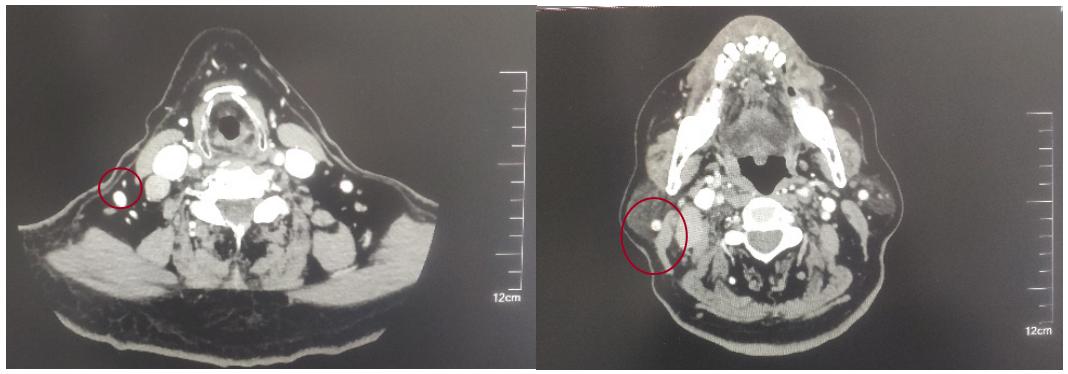

2022-05-05鼻咽部增强CT示:鼻咽CA并左侧翼腭弓、海绵窦受侵,伴邻近蝶窦、左侧筛窦、枕骨斜坡、左侧框下裂骨质破坏;右侧颈部多发肿大淋巴结(最大2.4×1.4cm),考虑转移;2.双侧梨状窝闭塞。

后患者至江苏省肿瘤医院放疗科就诊,2022-06-06完善头颅MR检查:

修正诊断: 鼻咽癌T3N1M0,Ⅲ期。